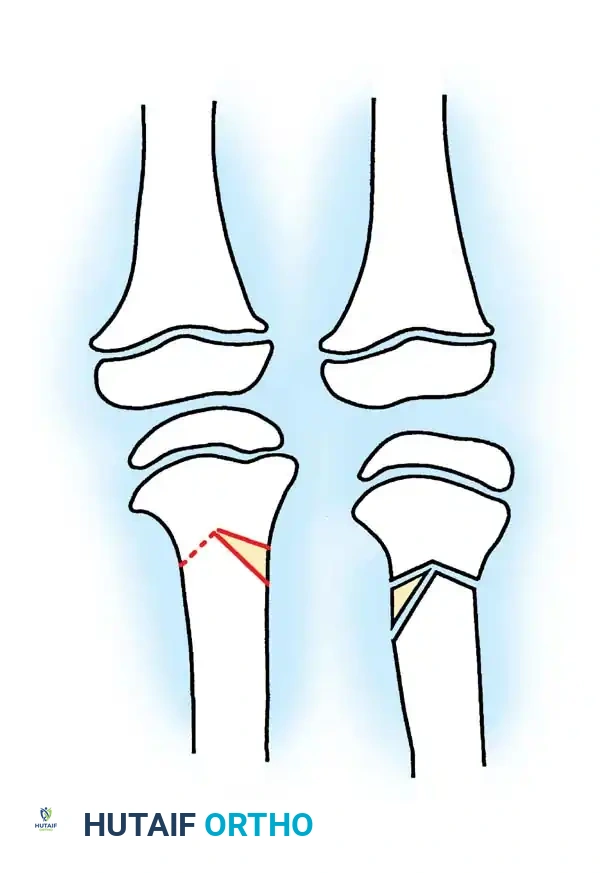

Advanced Disease: Intraepiphyseal Osteotomy and Medial Plateau Elevation

For older patients with severe, neglected deformities (Langenskiöld grades V and VI) where bracing and standard osteotomies have failed, the joint line is severely distorted. The medial femoral condyle sinks into a profound epiphyseal defect, causing severe joint instability.

In these advanced cases, a standard metaphyseal osteotomy will correct the mechanical axis but will leave the joint line unacceptably oblique, leading to early osteoarthritis.

Therefore, a double-elevating osteotomy is required:

1. Intraepiphyseal Osteotomy: To elevate the depressed medial tibial plateau and reconstruct the horizontal joint line.

2. Metaphyseal Valgus Osteotomy: To correct the diaphyseal varus angulation.

Schoenecker et al. reported successful elevation of the medial tibial plateau in patients aged 10 to 13 years with average preoperative varus deformities of 25 degrees. The procedure involves an osteotomy through the epiphysis, elevating the medial plateau to match the lateral plateau, and supporting the elevation with structural bone graft.

Surgical Warning: Intraepiphyseal osteotomies carry a high risk of intra-articular fracture, avascular necrosis of the elevated fragment, and permanent physeal arrest. Meticulous fluoroscopic guidance and rigid fixation are absolute requirements.